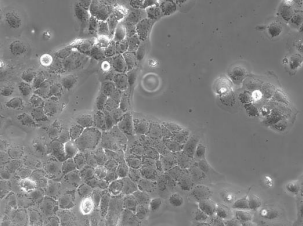

CaSki细胞是从小肠肠系膜转移灶的细胞中建立的。据报道,CaSki细胞含有完整的HPV-16(每个细胞大约600个拷贝)和HPV-18相关序列。

| 细胞形态 | 上皮细胞样 |

| 生长特性 | 贴壁细胞 |